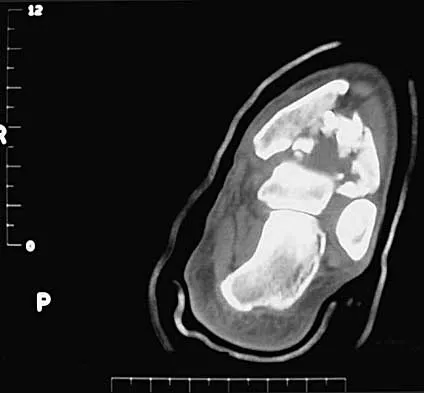

A 14-year-old boy reports pain in the distal thigh. He denies any history of trauma. Examination reveals tenderness and swelling of the distal thigh without effusion. A radiograph and CT scan are shown in Figures 10a and 10b. A biopsy specimen is shown in Figure 10c. Management should consist of

Explanation

Based on these findings, the patient has an aneurysmal bone cyst. Frequently, fluid-fluid levels can be detected on MRI or CT images. The histologic results show a lesion that consists of cavernous spaces filled with blood. The lining of the cavity contains spindle cells, multinucleated giant cells, and reactive bone. Curettage and bone grafting is the preferred treatment method. Without treatment, these lesions can become quite large and destructive. Radiation therapy is not recommended for resectable lesions. Chemotherapy is not required for these benign lesions. Simon MA, Springfield DS, et al: Common Benign Bone Tumors: Surgery for Bone and Soft Tissue Tumors. Philadelphia, PA, Lippincott Raven, 1998, pp 194-200.